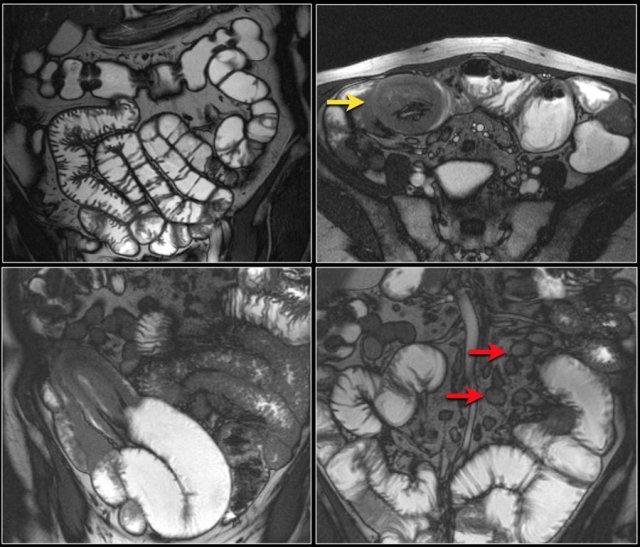

Chuỗi xung T1W sau tiêm thuốc tương phản từ có fat-sat (trái) và chuỗi xung T2W (phải) cho thấy một khối gây tắc nghẽn ở hỗng tràng với bờ dạng vai (mũi tên).

Có giãn ruột trước chỗ hẹp.

Các hình ảnh phía trên cho thấy một khối hình vòng ở đoạn gần hỗng tràng có tăng hấp thu FDG (mũi tên vàng).

Các hình ảnh MRI phía dưới cho thấy cùng khối hỗng tràng đó với bờ dạng vai và hạch to mạc treo (mũi tên đỏ), phù hợp với ung thư biểu mô tuyến.